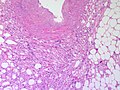

Micrograph of an angiomyolipoma - showing the three components (blood vessels (angio-) - left top, muscle (myo-) - elsewhere, fat (lipoma) - right bottom). H&E stain. | |

| LM | smooth muscle, adipose tissue (not always present), abundant blood vessels |

Features:

- Smooth muscle.

- Adipose tissue - not always present[11] - key feature.

- Abundant blood vessels.